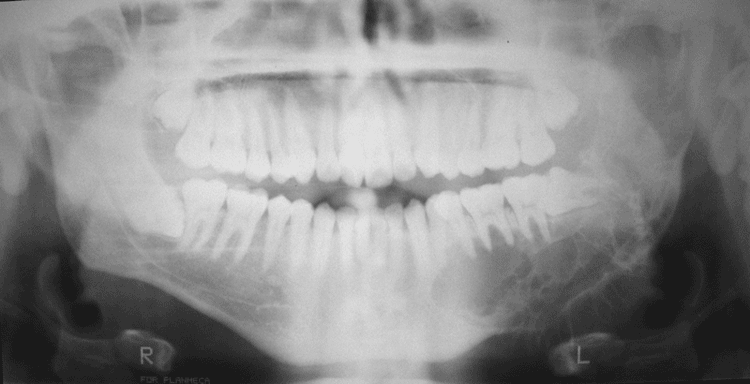

Radiology of the case:

Panoramic radiography shows a radiolucent, multilocular mass that expanded the left ramus (A). It involves the ramus tooth #17 to #21 and also extends into the left condyle. The margin of the lesion is scalloped and non-sclerotic. No periosteal reaction is present. Some fine trabeculae are present but no radiodensity suggestive of mineralized content are present.

The radiographic features of MOJs are not unique. Typically, they occur as expansile radiolucent unilocular or multilocular lesions with irregular or scalloped margin. They are often but not always found in tooth bearing regions 5. The larger ones tend to be multilocular 4. A sclerotic margin is not a typical feature. There may be thin trabeculae of residual bone that are often arranged at right angles to one another within the radiolucent defect but mineralized tissue is not present. This feature distinguishes it from many odontogenic lesions such as calcifying odontogenic tumors and osteoblastomas that contain mineralized tissue. The radiographic features also overlap with many other agnathic lesions. Large MOJs of the mandible may have a “soap bubble” appearance that mimic ameloblastomas. Giant-cell granulomas also have radiological and clinical features similar to MOJs.